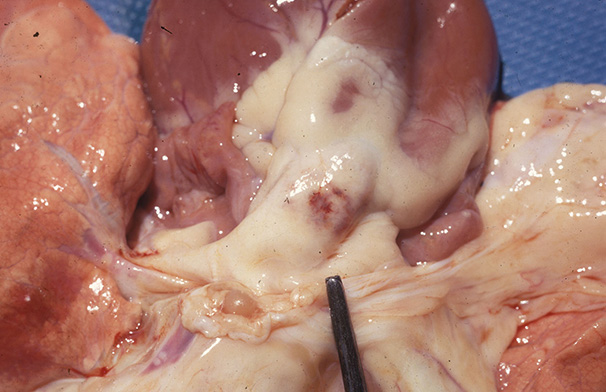

Bluetongue in a sheep : severe hydropericardium

Veterinary tropical diseases, Infectious diseases, Bluetongue